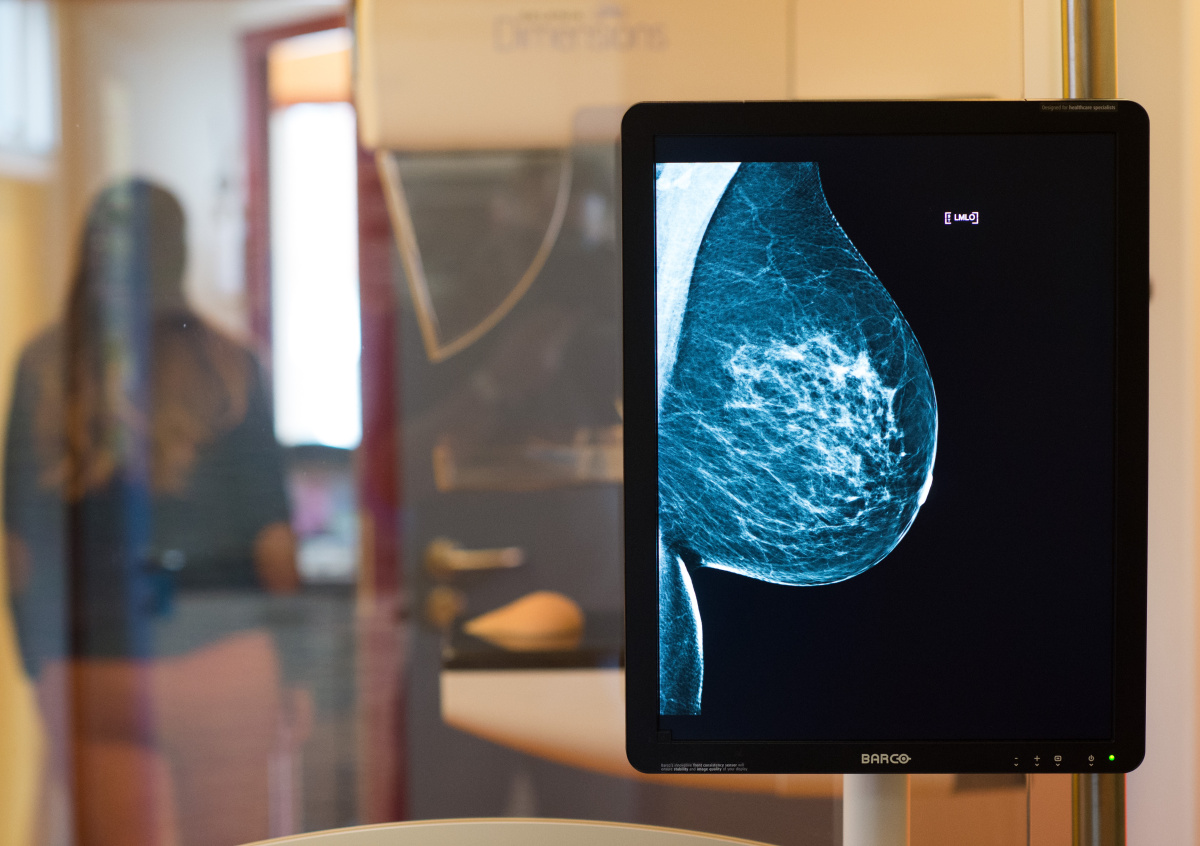

Искусственный интеллект научился распознавать рак лучше экспертов

Система искусственного интеллекта, разработанная при участии компании Google, оказалась результативнее специалистов в распознавании рака молочной железы.

В ходе эксперимента модель ИИ проанализировала свыше 25 тысяч женских рентгенограмм в Великобритании и трёх тысяч в США. Система установила наличие онкологии с меньшим количеством ложноположительных и ложноотрицательных результатов, чем эксперты.

В частности, снижение недостоверных положительных показаний составило 5,7% для США и 1,2% для Великобритании. По ложноотрицательным результатам ИИ превзошёл экспертов на 9,4% в США и 2,7% в Великобритании.